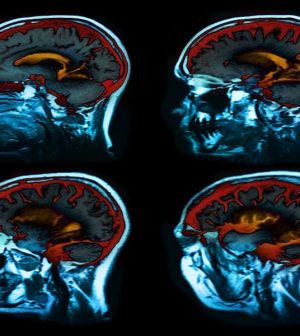

Their study included nearly 1,400 patients in Switzerland, average age 72, who had atrial fibrillation and underwent MRI brain scans. None had suffered a stroke or mini-stroke (transient ischemic attack — TIA).

Forty-one percent had at least one type of previously unknown brain damage. Of these, 15 percent had a cerebral infarct, which is an area of dead tissue in the brain; 19 percent had small bleeds in the brain (microbleeds); and 16 percent had small deep brain lesions called lacunes.